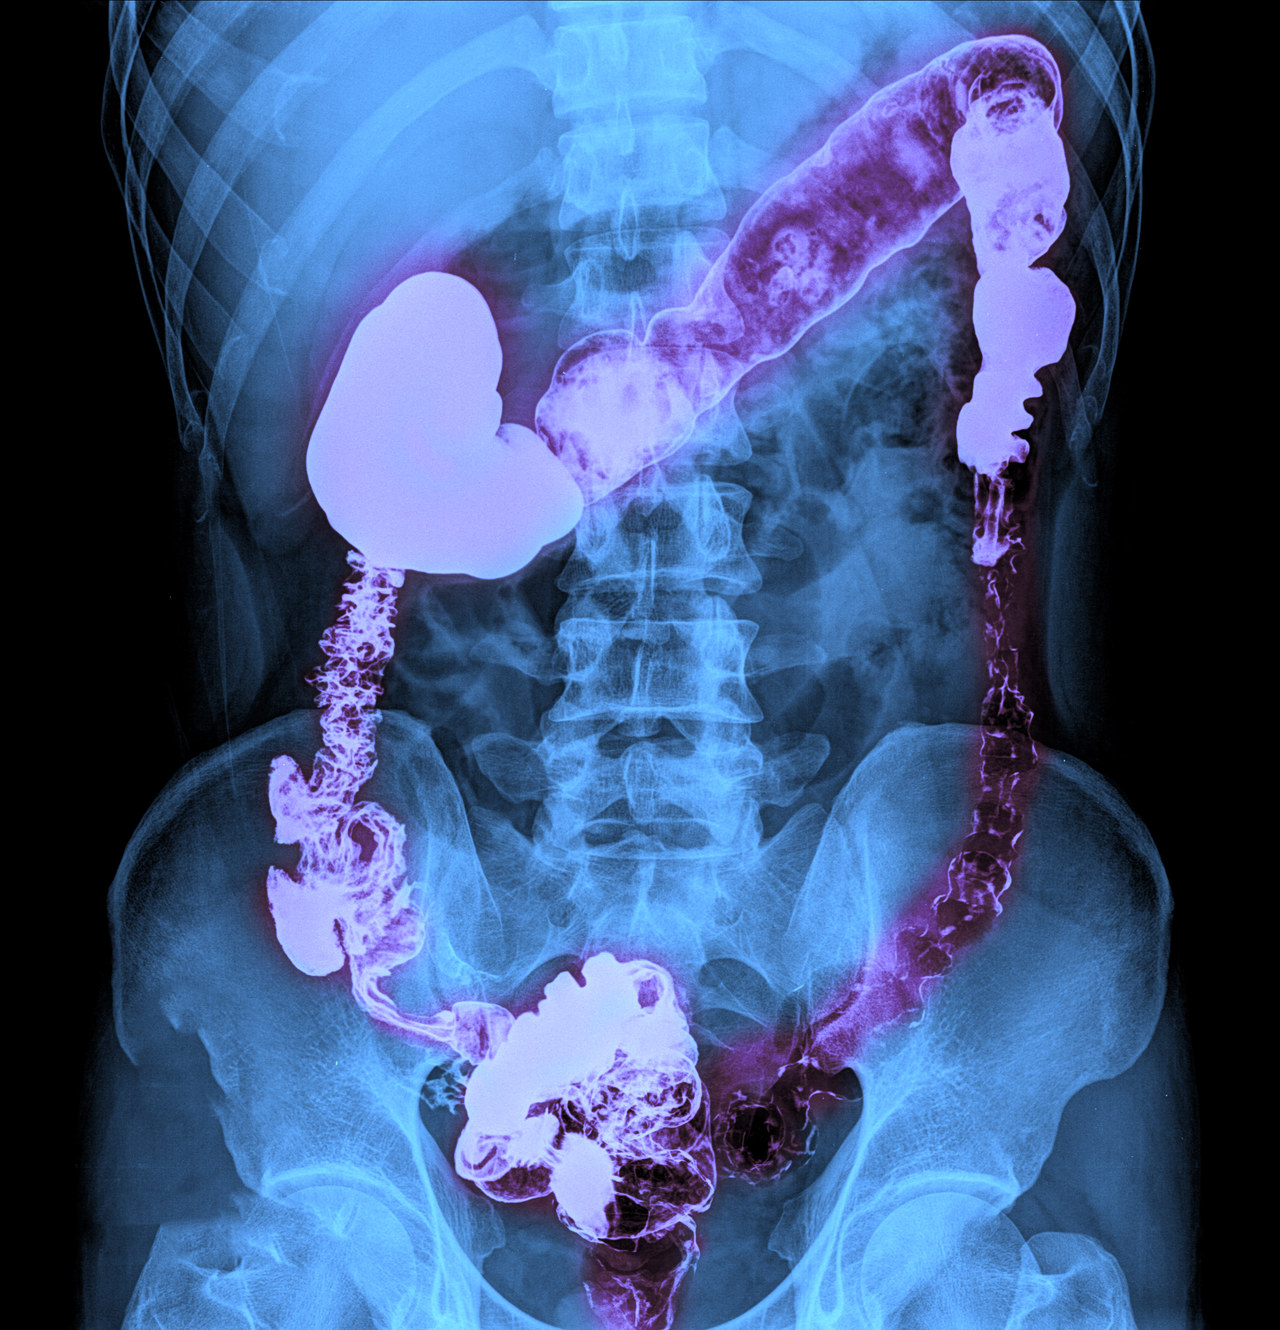

结肠恶变的治疗策略

结肠恶变(结肠癌)的治疗需要根据患者的具体病情、肿瘤的分期、位置以及患者的整体健康状况来制定个体化的治疗方案。以下是常见的治疗方法: